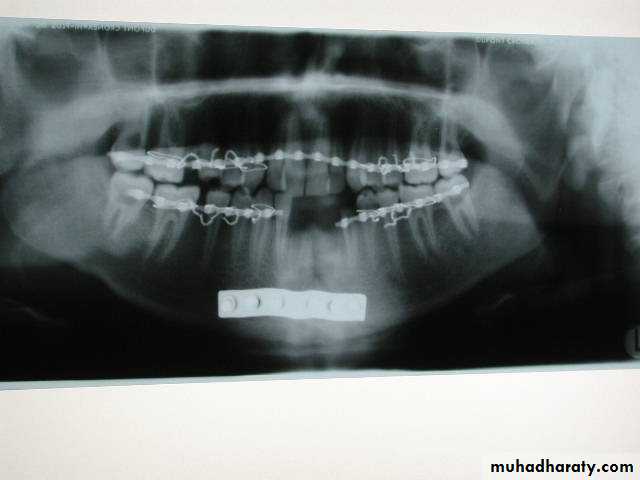

• Closed reduction with indirect skletal fixation : Dependent on splinting of the mandible to maxilla to restore centric occlusion (maximal intercuspation)• 1. IMF ( Prefabricated arch bar )

Arch bars

Jelenko

Erich pattern

German silver notched

▶ IMF prior to rigid fixation

▶ For the purpose of close reductionClose reduction

• Open reduction

• Intraosseous wiring + IMF (3 to 8 weeks)• Rigid internal fixation (plating) these method use bone plates, bone screws or both to fix the fracture.

Plating

If teeth are present IMF is done ; then incision is made and bone is reached either extra orally or intra orally.The fractured ends are approximated and screw holes are made such that at least 2 screws can be placed on either side of the fracture.